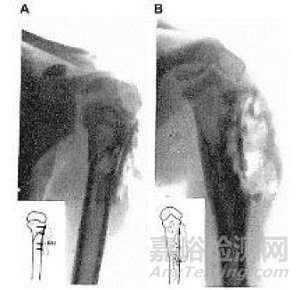

早在1907年,Lambotte就使用鐵絲環扎術和一塊帶有六個鋼螺絲的鎂板來固定骨折的小腿,但是由于鎂和鐵接觸后發生電化學反應,加速了鎂的腐蝕,術后一天即觀察到了大量的皮下氣腔,并伴有局部有腫脹和疼痛。因此在排除了鎂和其他金屬混用后,Lambotte與其助手Jean Verbrugge用鎂釘治愈了4例兒童肱骨髁骨折(圖1),除發現氣泡產生外,沒有其它不良反應發生。Jean Verbrugge在接下來的幾年里,采用鎂及其合金(AZ63和Mg-8wt.%Al)進行了25例骨折治療的臨床實驗,如圖2所示。由于鎂在植入后的快速腐蝕降解,鎂板和鎂釘固定系統植入三周后,骨折線即消失不見。除此之外,有病人反映,植入部位會有暫時的麻木感覺,但沒有組織感染跡象或不良反應發生。在這些病例中,因植入尺寸以及位置不同,鎂在人體內在三個星期到一年最終吸收。McBride進行的臨床應用探索,如圖3所示,發現鎂可以加速治療初期結締組織的早期增殖和愈合組織的增生。1940年,Maier使用了由梭形鎂片制成的針治療肱骨骨折,并且在接下來的14年獲得良好的恢復。

圖2 A, B為采用鎂板和鎂釘為兒童的踝部骨折進行固定,(A)術后X光顯示有氣泡形成;(B)鎂板術后3周已基本腐蝕降解。(C)為采用鎂釘治療兒童髁部肱骨骨折的術后X光照片,顯示植入早期皮下有氣泡形成。